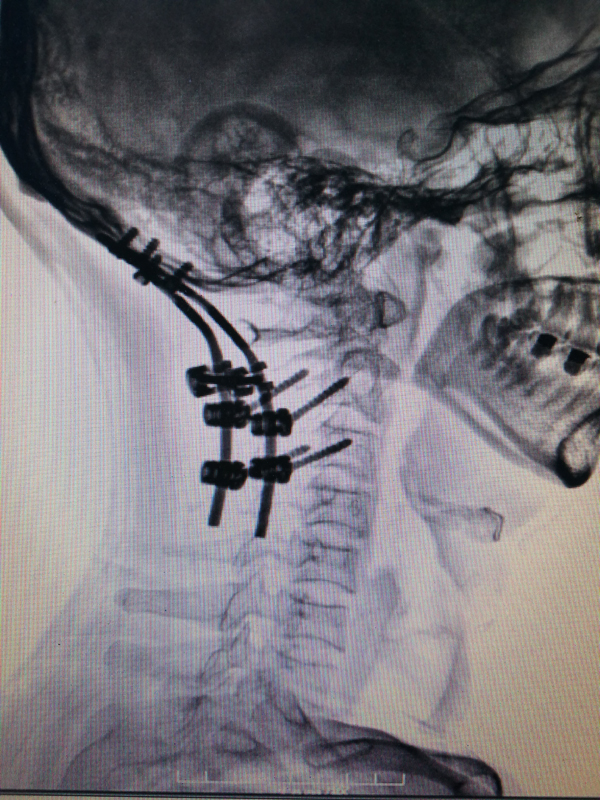

近日,武安市中醫(yī)院骨傷一科成功完成一例頸枕融合內(nèi)固定治療頸椎高位骨折脫位的手術(shù)。患者郭某,男性,因外傷導(dǎo)致頸部疼痛劇烈,活動障礙,尚無肢體麻木、癱瘓等神經(jīng)癥狀。入院后經(jīng)頸椎核磁共振,X光片等檢查,明確診斷:1、樞椎齒狀突骨折;2、寰樞關(guān)節(jié)脫位。因骨折部位特殊,手術(shù)風(fēng)險較高,患者可能并發(fā)高位截癱。骨傷一科侯永生主任組織全科討論,制定詳細治療方案。首先采取頸椎枕頜帶持續(xù)牽引的方式保持骨折處穩(wěn)定,以免造成二次損傷。待一切術(shù)前準備完善后,在全麻下進行“經(jīng)頸椎后路行樞椎齒狀突骨折及寰樞關(guān)節(jié)脫位切開復(fù)位”,并予頸枕融合內(nèi)固定。術(shù)后恢復(fù)良好,繼續(xù)予頸托外固定12周。

術(shù)前

術(shù)后